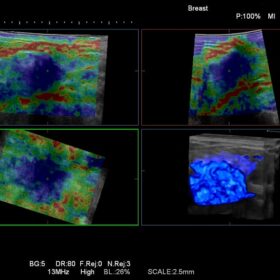

Ultrasound HI VISION Ascendus – Image Gallery and Videos

Radiology 2D, Color, Contrast, Elasto and RVS mode

- Enhanced contrast imaging sensitivity across a wide range of general abdominal and high frequency applications. With Hitachi’s dynamic Contrast Harmonic Imaging (dCHI) software

- High performance imaging underpinned by new leading edge technologies such as 4D Real-time Tissue Elastography (RTE). Inflow-time mapping (ITM) of contrast agents

Expert imaging modalities such as Real-time Tissue Elastography (RTE) and dynamic Contrast Harmonic Imaging (dCHI). These modalities complement the high definition imaging for improved diagnostic confidence and maximum therapeutic potential.